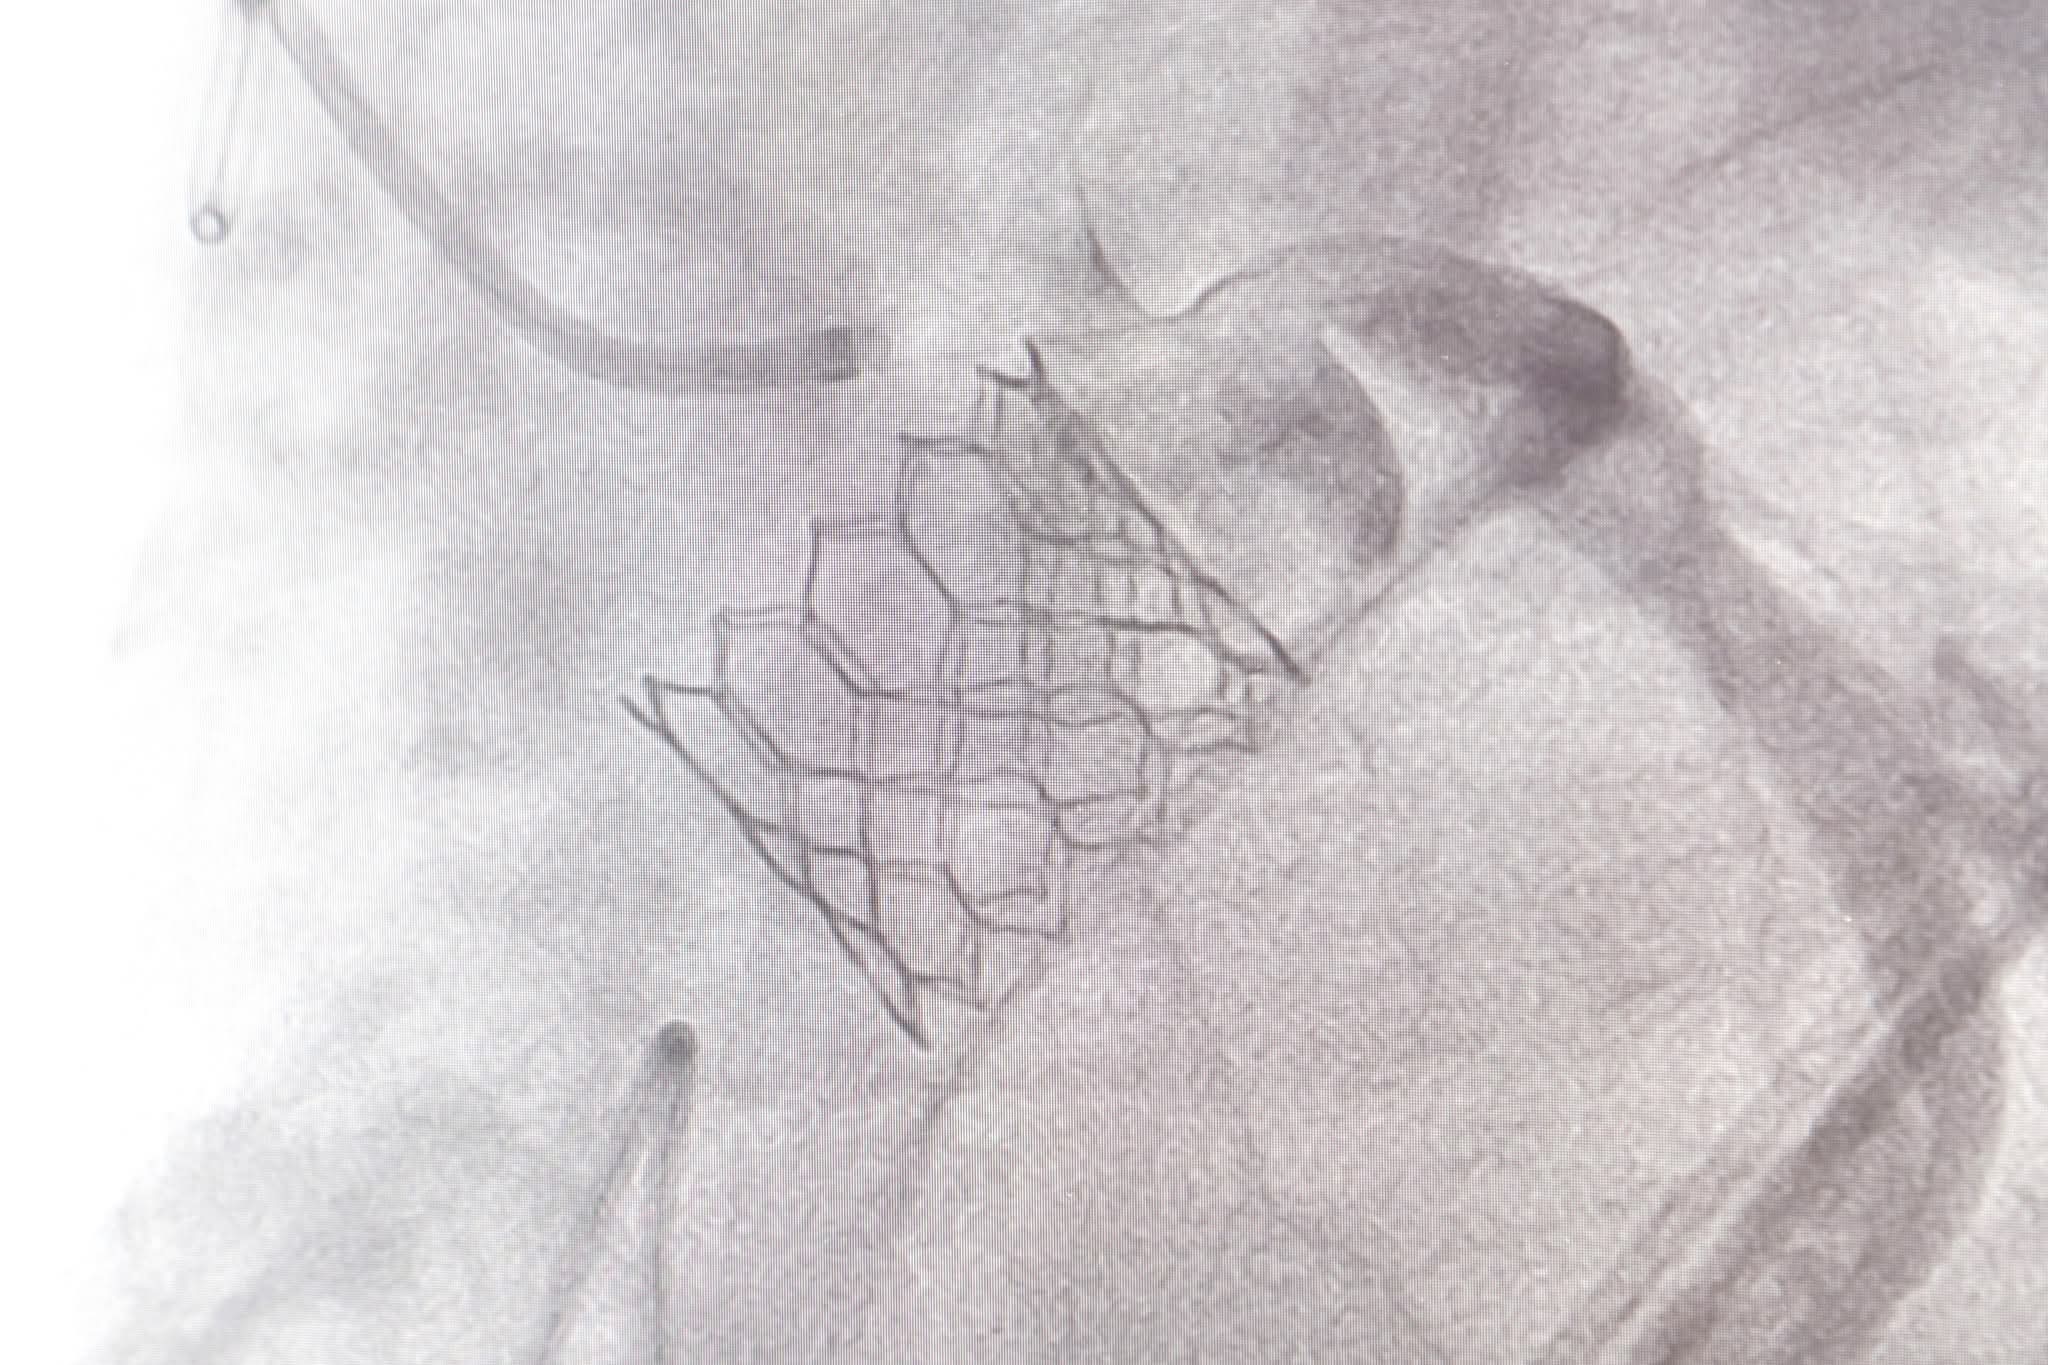

เมื่อเวลา 11.30 น.วันที่ 4 ธ.ค.2568 นพ.ดนณ แก้วเกษ อายุรแพทย์หัวใจและหลอดเลือด เปิดเผยว่า โรคลิ้นหัวใจเอออร์ติกตีบขั้นรุนแรงเป็นภาวะที่พบได้มากในผู้สูงอายุ และอาจนำไปสู่อาการเหนื่อยง่าย เจ็บหน้าอก เวียนศีรษะ หรือภาวะหัวใจล้มเหลวได้ การรักษาแบบดั้งเดิมคือการผ่าตัดเปิดหน้าอกเพื่อเปลี่ยนลิ้นหัวใจ แต่ผู้ป่วยบางรายมีความเสี่ยงสูง ไม่เหมาะกับการผ่าตัด ดังนั้นวิธีการรักษาแบบ TAVI (Transcatheter Aortic Valve Implantation) หรือการเปลี่ยนลิ้นหัวใจเอออร์ติกโดยไม่ต้องผ่าตัดเปิดหน้าอก จึงเข้ามามีบทบาทสำคัญ ซึ่งข้อดีของ TAVI คือไม่ต้องเปิดหน้าอก ไม่ต้องหยุดหัวใจ โดยแพทย์จะผ่าตัดใส่ลิ้นหัวใจเทียมผ่านทางหลอดเลือดแดงที่ขาหนีบ ทำให้ผู้ป่วยฟื้นตัวได้อย่างรวดเร็ว หลายรายกลับบ้านได้ภายใน 2–3 วัน

“ศูนย์หัวใจสิริกิติ์ฯ ใช้เทคโนโลยีลิ้นหัวใจรุ่นใหม่ที่พัฒนาให้วางตำแหน่งได้แม่นยำ ลดความเสี่ยงของภาวะแทรกซ้อน เช่น เลือดออก หลอดเลือดได้รับบาดเจ็บ หรือการนำไปสู่ภาวะการเต้นผิดจังหวะ ทีมแพทย์ Heart Team ซึ่งประกอบด้วยแพทย์โรคหัวใจ แพทย์หัตถการ แพทย์ศัลยกรรมหัวใจ วิสัญญีแพทย์ และทีมพยาบาลเฉพาะทาง จะร่วมกันวางแผนการรักษาและประเมินอย่างละเอียดในผู้ป่วยแต่ละราย เพื่อให้ได้ผลลัพธ์ที่ปลอดภัยที่สุด”